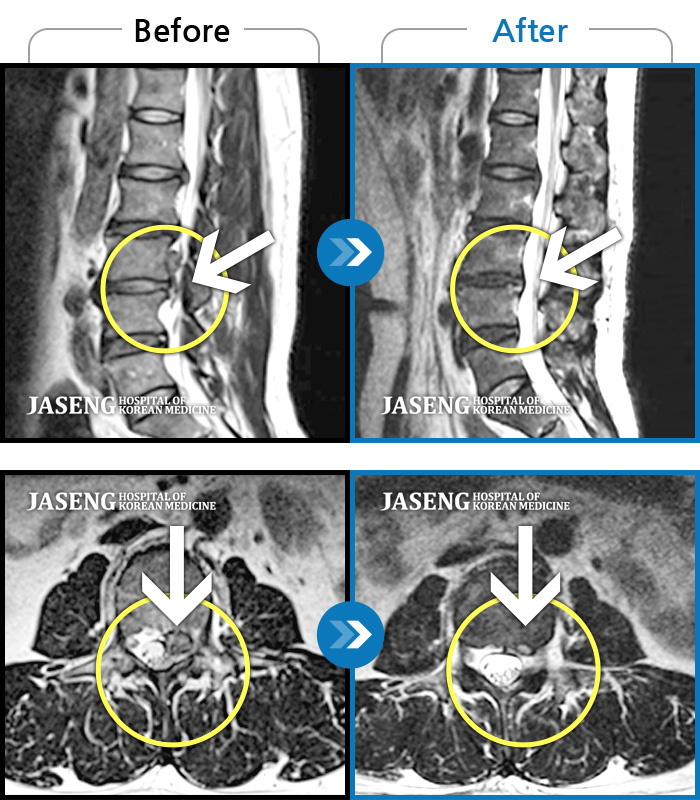

Xray 와 MRI 검사를 받았고

4번5번 척추사이 협착증과 유종이 원인이라고 하면서

한방 비수술치료로 2달동안 치료하면 나을 수가 있다고 말씀하셨고, 만약 한방치료로도 낫지 않으면 큰 대학병원 수술을 받아야 한다고 하면서 한방 비수술 치료를 권장해 주셔서, 박정우원장님의 치료를 받기 시작하였다.

12월20일까지 두 달 정도 치료를 마친 결과,

거의 정상상태로 회복 되었으며, 현재는 집에서 꾸준하게 체조와 가벼운 운동으로 관리하고 있습니다.